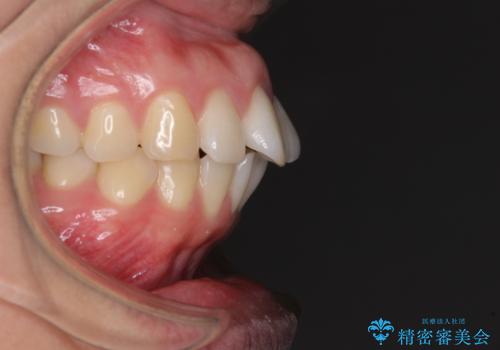

- 前歯の出っ歯と口元の閉じにくさを気にして来院された患者様です。

口元を積極的に引っ込めるために、上下左右の小臼歯4本を抜歯することとしました。

4本の歯を抜歯したことで、飛び出していた口元が引っ込み、横顔が大きく改善されました。

咬み合わせが悪化することのないようにスペースを閉じていくことができ、比較的スムーズに治療を進めることができました。